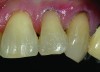

Shade selection is always completed before initiating treatment; this is important to develop the proper shade-layering sequence. Composite shades were placed directly on the tooth and shades that matched the areas of the tooth being restored were chosen (Figure 2). To achieve an invisible Class V restoration, a more complex layering process is needed to blend the composite resin.

Total removal of the decay was performed. To keep the preparation minimally invasive, a caries indicator (Seek®, Ultradent Products, Inc., www.ultradent.com) was used so that only the infected dentin was removed. Minimally invasive burs (Micro Prep Kit, Komet USA, www.kometusa.com) were used, which are helpful when minimal tooth removal is an objective (Figure 3). A long-bevel margin (889M-007, Komet USA) was then created along the facial side so that the final composite resin could be blended to the existing dentition. A thin layer of resin-modified glass ionomer (RMGI) (GC Fuji II™ LC, GC America Inc.) was sculpted and light-cured to cover the affected dentin.